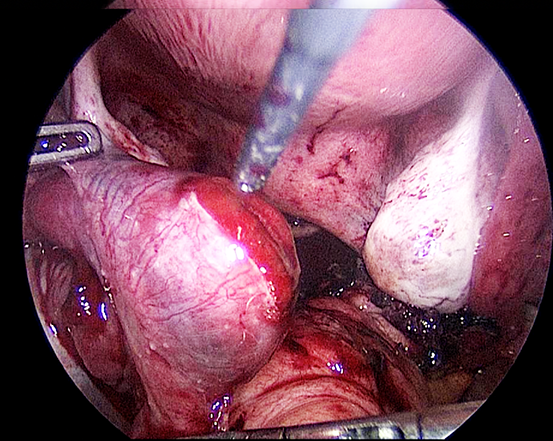

Kasus 26.2

Reseksi laparoskopi kornu kehamilan ektopik

Pada tahun 2009 nyonya UDS datang mengunjungi saya , dia telah menikah 3 tahun dan dia tidak bisa hamil. Histerosalpingogram yang dilakukan di rumah sakit yang lain menunjukkan kedua tubanya tersumbat / terblokir. Dia menjalani laparoskopi , dan laparoskopi menunjukkan ukuran rahim yang normal. Kedua tuba nya normal dan dipatenkan setelah insulfasi tuba dilakukan dibawah tekanan. Dia hamil secara spontan 2 bulan setelah menjalani laparoskopi namun sayangnya kehamilan berakhir dengan aborsi yang terlewatkan. Dia telah menjalani evakuasi hasil konseptus. Pasca operasi , keadaan dia baik-baik saja akan tetapi tidak dapat hamil. Dia telah diberikan beberapa siklus klomifen sitrat namun tanpa membuahkan hasil. Pada tahun 2011, dia menjalani siklus inseminasi intrauterin setelah diberikan suntikan hormon perangsang folikel ( FSH ). Setelah prosedur dilakukan , dia hamil akan tetapi sayangnya kehamilan itu adalah kehamilan ektopik. Dia menjalani reseksi laparoskopi kornu kanan kehamilan ektopik di tahun 2011 ( Gambar 26.7 – 26.11 ) ( simak video 26.3 ). Pasca operasi di tahun 2013 dia menjalani histerosalpingografi dan menunjukkan bahwa tuba kiri tidak paten. Dia dapat hamil setelah menjalani IVF.

Pembahasan

Kornu kehamilan ektopik tidaklah umum. Biasanya didiagnosisnya terlambat karena pasien dengan kondisi seperti ini tidak memliki banyak gejala-gejala. Pecahnya kehamilan ektopik pada kornu dapat menyebabkan pendarahan yang berlebihan. Pada pasien ini diagnosis dilakukan lebih awal karena dia menjalani IUI dan berada dalam pengawasan secara teratur. Eksisi telah dilakukan dengan berhasil secara laparoskopi.